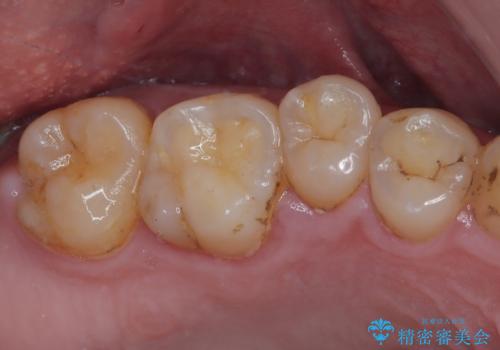

部分矯正を行ったこと治療期間は長くなりましたが、違和感のない咬み合わせを達成することができました。